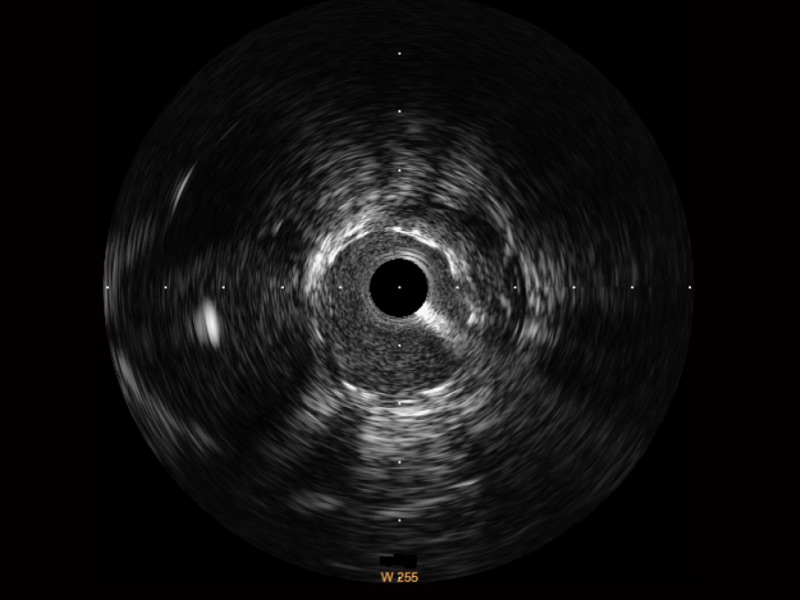

竞技宝(JJB)官方网站宽频IVUS图像

传统IVUS图像

对比传统IVUS导管成像,竞技宝(JJB)官方网站宽频IVUS图像的近场支架梁显影更细腻,远场中膜外血管仍清晰可辨,兼顾远中近,兼顾分辨力与穿透深度